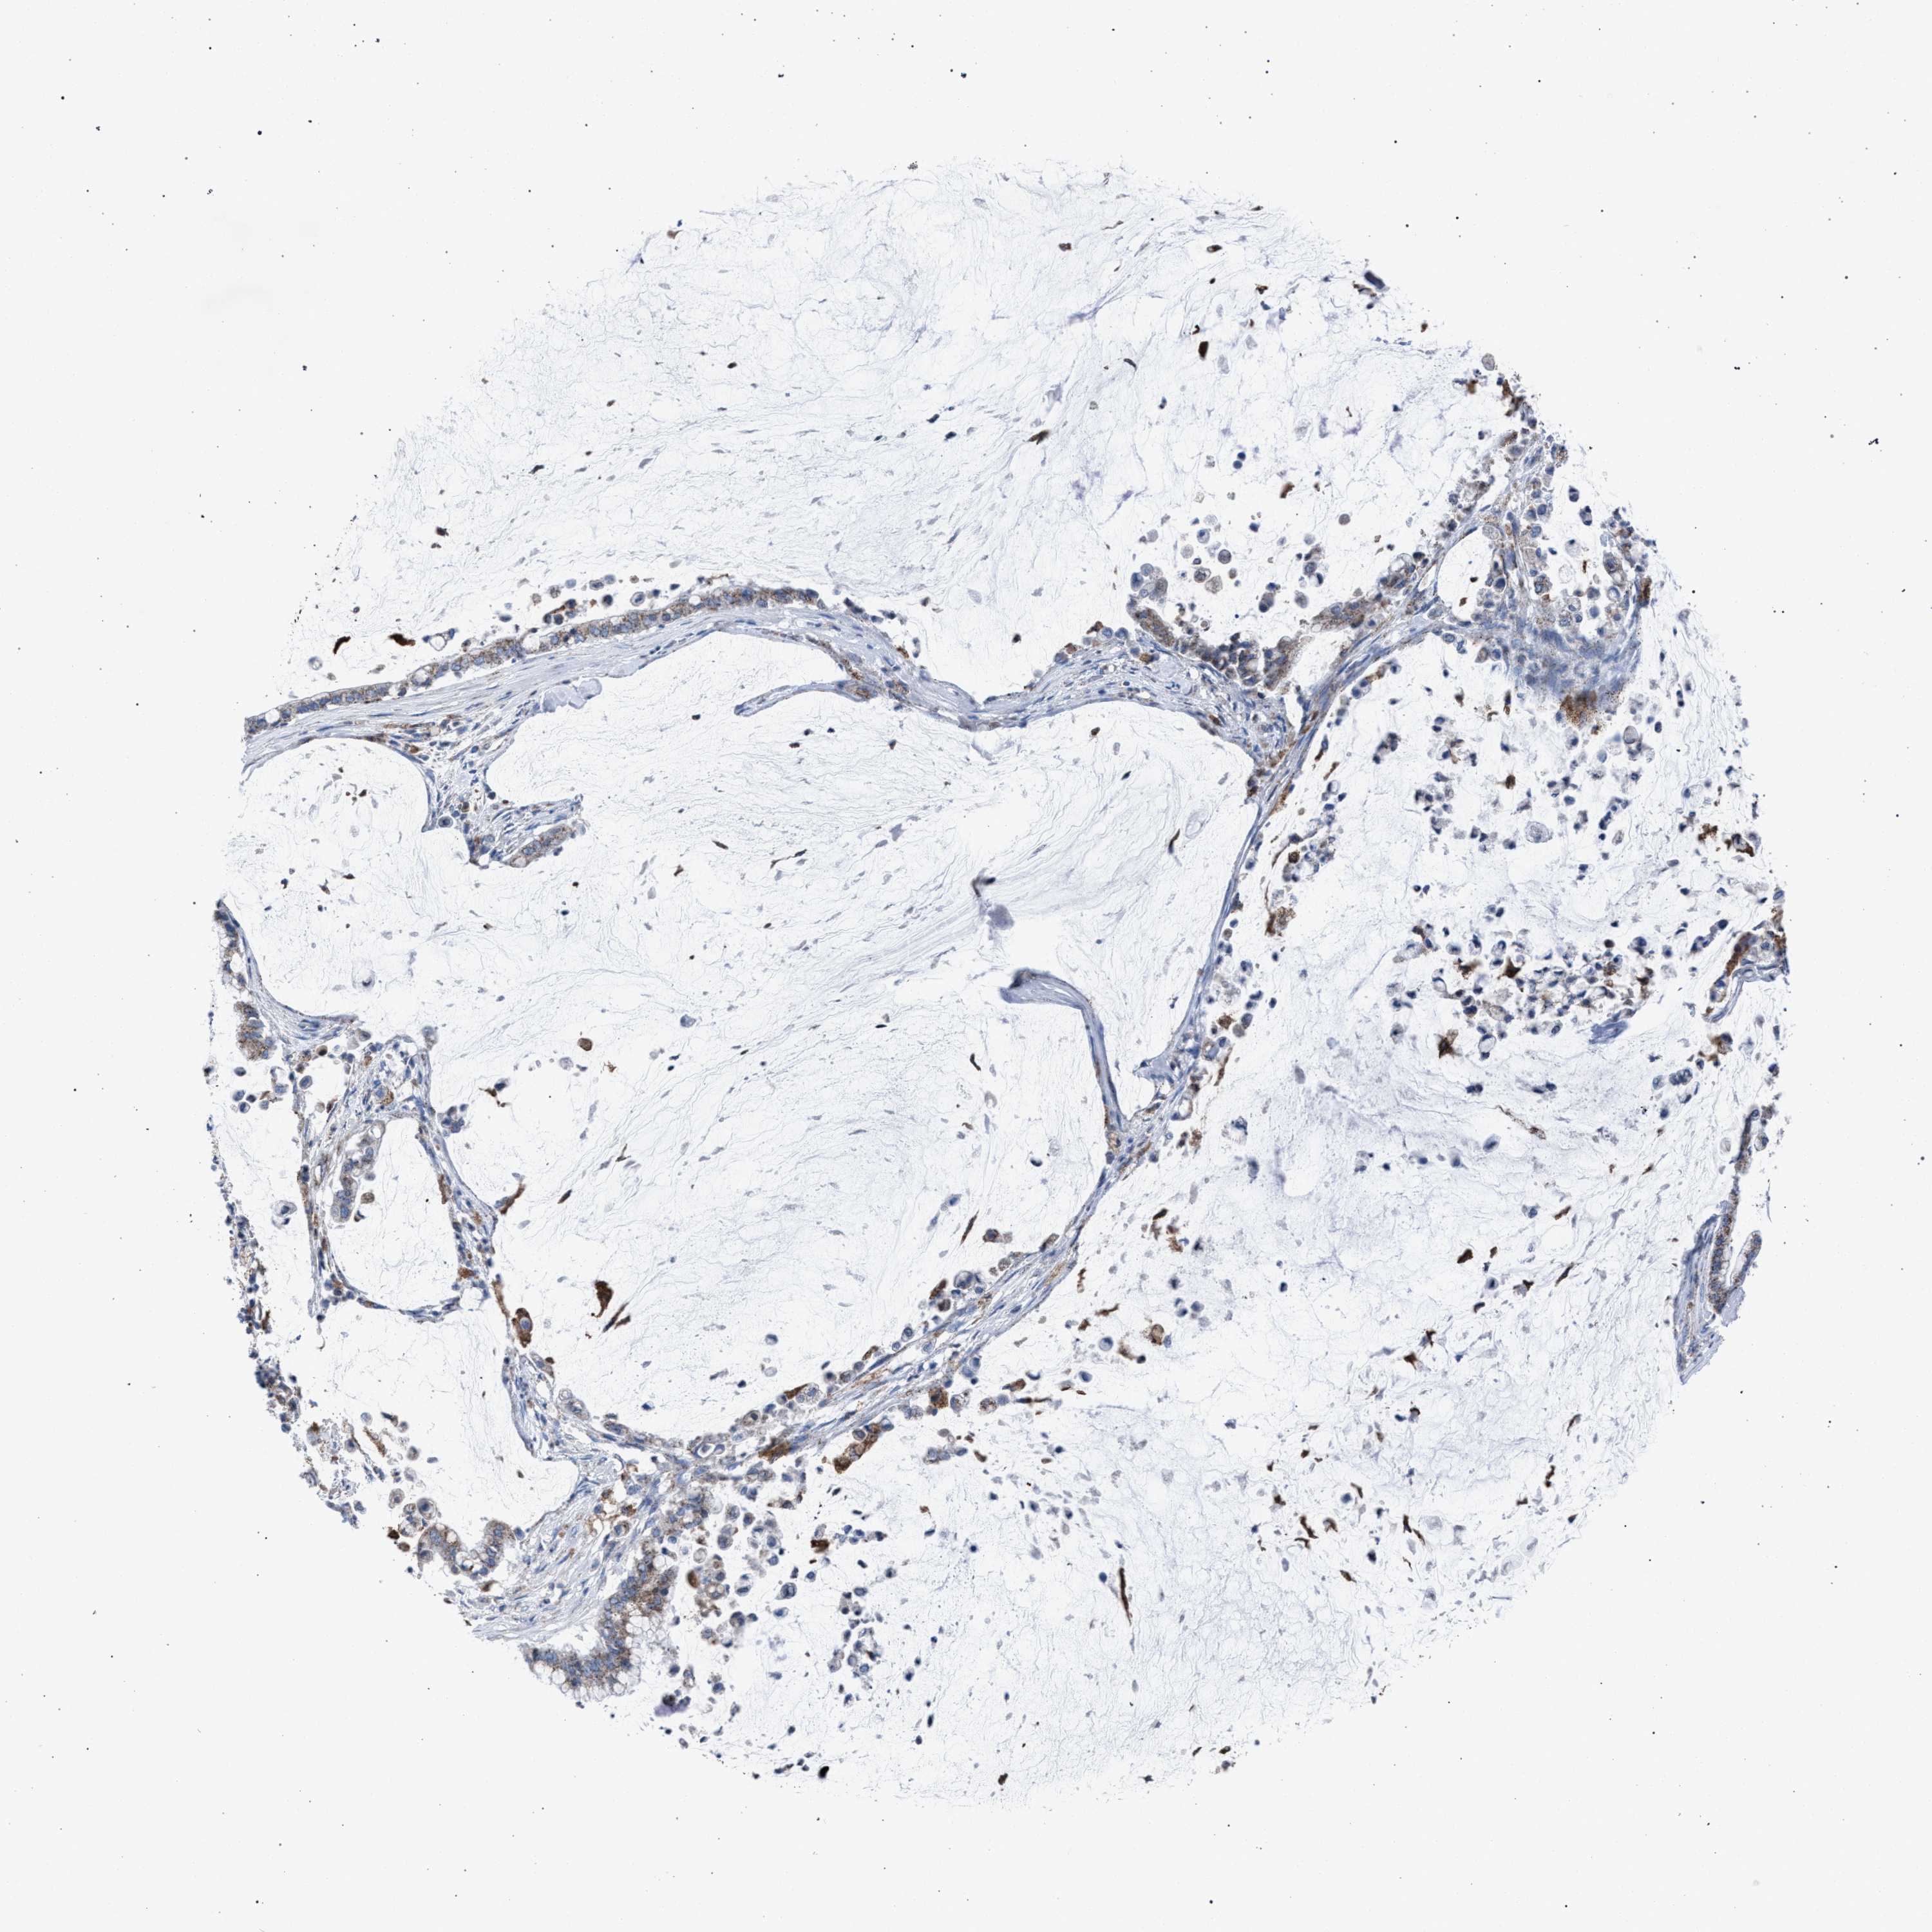

PANCREATIC CANCER - Protein expressioni

A mouse-over function shows sample information and annotation data. Click on an image to view it in a full screen mode. Samples can be filtered based on level of antibody staining by selecting one or several of the following categories: high, medium, low and not detected. The assay and annotation is described here.

Note that samples used for immunohistochemistry by the Human Protein Atlas do not correspond to samples in the TCGA dataset.

Antibody stainingi

Antibody staining in the annotated cell types in the current human tissue is reported as not detected, low, medium, or high, based on conventional immunohistochemistry profiling in selected tissues. This score is based on the combination of the staining intensity and fraction of stained cells.

Each image is clickable and will lead to virtual microscopy that enables deeper exploration of all samples and also displays staining intensity scores, fraction scores and subcellular localization as well as patient and tissue information for each sample.

Antibody HPA021302

Antibody HPA021311

Antibody HPA021479

Staining

High

Medium

Low

Not detected

Intensity

Strong

Moderate

Weak

Negative

Quantity

>75%

75%-25%

<25%

None

Location

Nuclear

Cytoplasmic/membranous

Cytoplasmic/membranous,nuclear

Adenocarcinoma, NOS